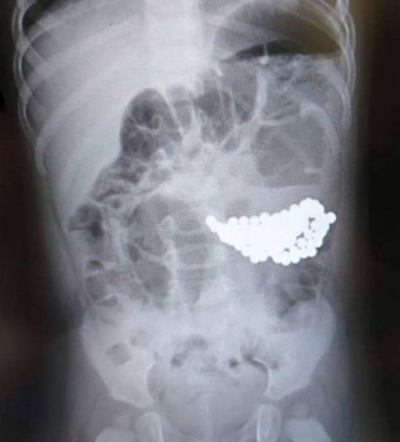

U RUSKOM gradu Gubkinski u Jamalskonenečki autonomnom okrugu, dvogodišnje dijete preminulo je nakon što je progutalo 18 malih magneta, izvijestio je info24.ru. Roditelji su to primijetili tek nakon nekog vremena i odmah otišli u bolnicu, prenosi Telegram kanal “Real Noyabrsk”.

“Tragedija se dogodila u selu Purpe. Dvogodišnji Matvej progutao je 18 malih magneta koje je pronašao dok se igrao. Roditelji su odmah pozvali hitnu pomoć, ali dijete je preminulo tri sata kasnije”, navodi se u objavi.

Prema liječnicima, dijete je bilo u vrlo teškom stanju. Liječnici su uspjeli dijagnosticirati problem i pokušali su ga reanimirati, ali nisu uspjeli spasiti dječaka. Izvori URA.RU navode da lokalne pravosudne vlasti trenutno istražuju okolnosti ovog slučaja. Druge pojedinosti o incidentu zasad nisu dostupne., piše Index.